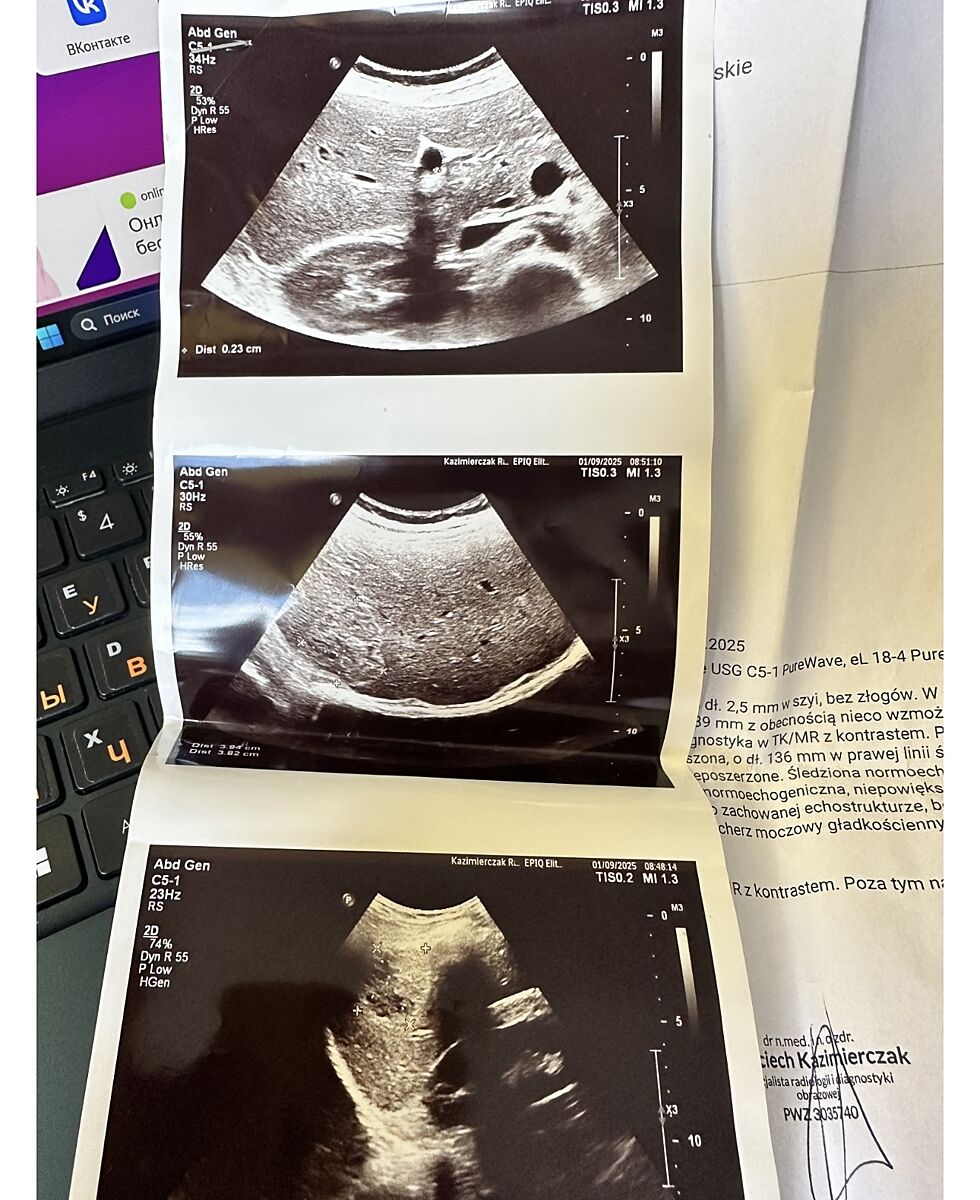

Автор, где ваше описание узи или что там делали по печени?

Вот

attached-photo